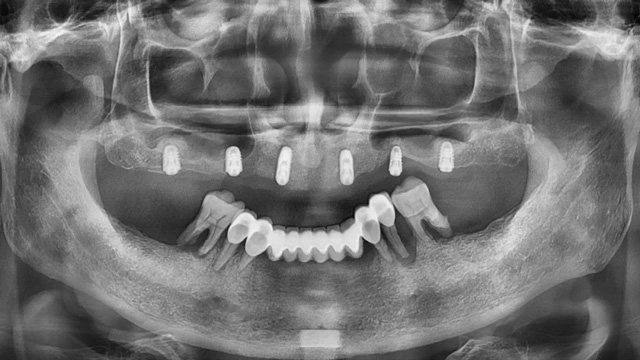

王先生全口種植后全景片(2024年4月/新橋口腔成都衣冠廟院區(qū))

由于王先生在上一家診所種下的6顆種植體比較短小,在力學(xué)方面達(dá)不到修復(fù)標(biāo)準(zhǔn),還有兩顆因?yàn)樗蓜?dòng)和頸部暴露無法使用,李陽軍醫(yī)生又加種了3顆更長更粗的,以確保長期穩(wěn)定性。由于骨量不足,有兩顆采用了傾斜植入以增加骨接觸的面積,目的也是為了更加穩(wěn)固,還有一顆因?yàn)樵恢霉橇刻睿臑樵谄渌恢梅N植,采取了高難度的術(shù)式。